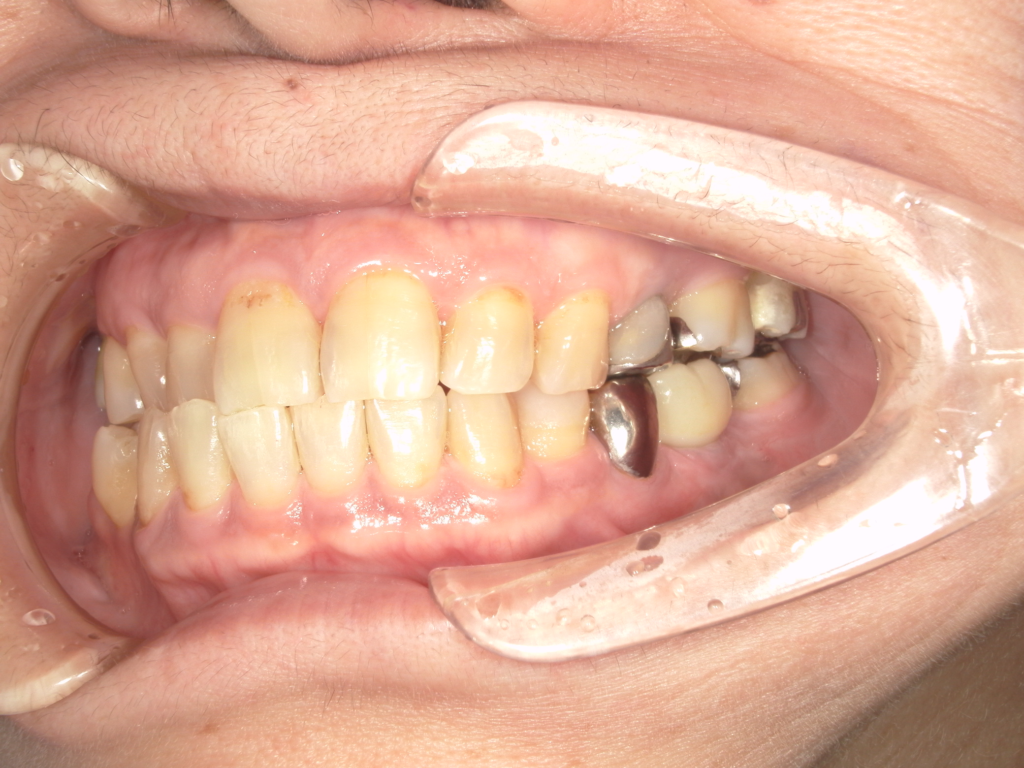

Y様インプラント実例 #44

左の上下の奥歯をインプラントで治療しています。

左下の奥歯は歯を抜くのと同時にインプラントの埋め込みを行っています。

被せものは上下、セラミックスで作っています。

治療前

治療後